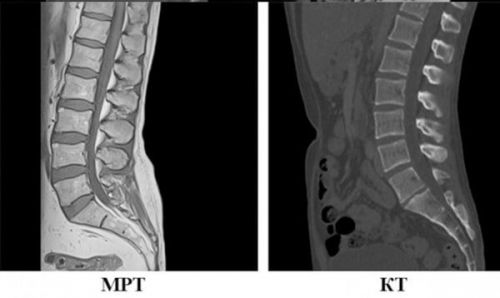

КТ – це комп’ютерна томографія. Процес проведення КТ схожий на МРТ: пацієнт лягає на рухомий стіл, що проводить крізь круглий КТ-сканер. При КТ використовуються рентгенівські промені, за допомогою яких лікар отримує 2D-зображення поперечних перерізів тих чи інших частин тіла під різними кутами. Далі ці зображення за допомогою комп’ютера трансформуються у 3D. У нейрохірургії КТ використовується для візуалізації кісток хребта та черепа (наприклад, при інсультах). До речі, сьогодні є й апарати МРТ, що також можуть все це показати.

МРТ – це магнітно-резонансна томографія. Людина лягає у довгий тунель (закритого чи відкритого типу). МРТ-сканер для візуалізації використовує радіохвилі і магнітне поле. Радіохвилі відбиваються від молекул води та жиру у тілі людини.

На комп’ютер надсилаються ці результати і створюється зображення необхідної ділянки тіла. МРТ використовують для візуалізації м’яких тканин (в нейрохірургії – це нерви, спинний і головний мозок, зв’язки, діагностика стенозів тощо).Отже, КТ – це той самий рентген, але потужніший. А МРТ – безпечніший, бо не дає опромінення, там працює звичайний магніт, а отже МРТ можна робити так часто, як це необхідно.